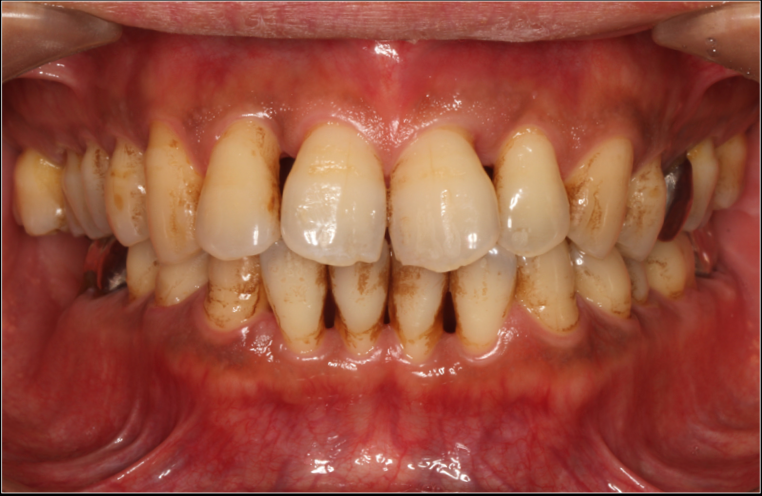

治療例

重度歯周病の症例